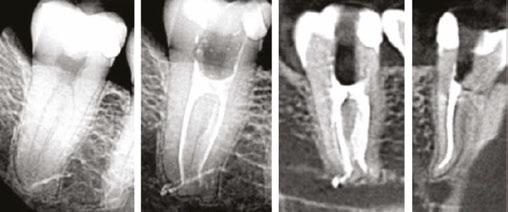

The XP-3D Finisher is indicated to be used (Figure 5):

1. After conventional NiTi instrumentation

2. After XP-3D Shaper+ especially in oval canals

3. In retreatment cases

4. In special anatomical cases such as internal resorptions, dens in dente, and immature roots

With the XP-3D Finisher in a clinician’s armamentarium, eliminating biofilm and maximizing disinfection is now possible in a minimally invasive fashion.

Figure 5: The XP-3D Finisher can be used in many situations. Its ability to expand and scrape the root canal walls make it an ideal instrument to remove biofilm and previous root canal filling as well to adapt and clean special anatomical cases such as a dens in dente